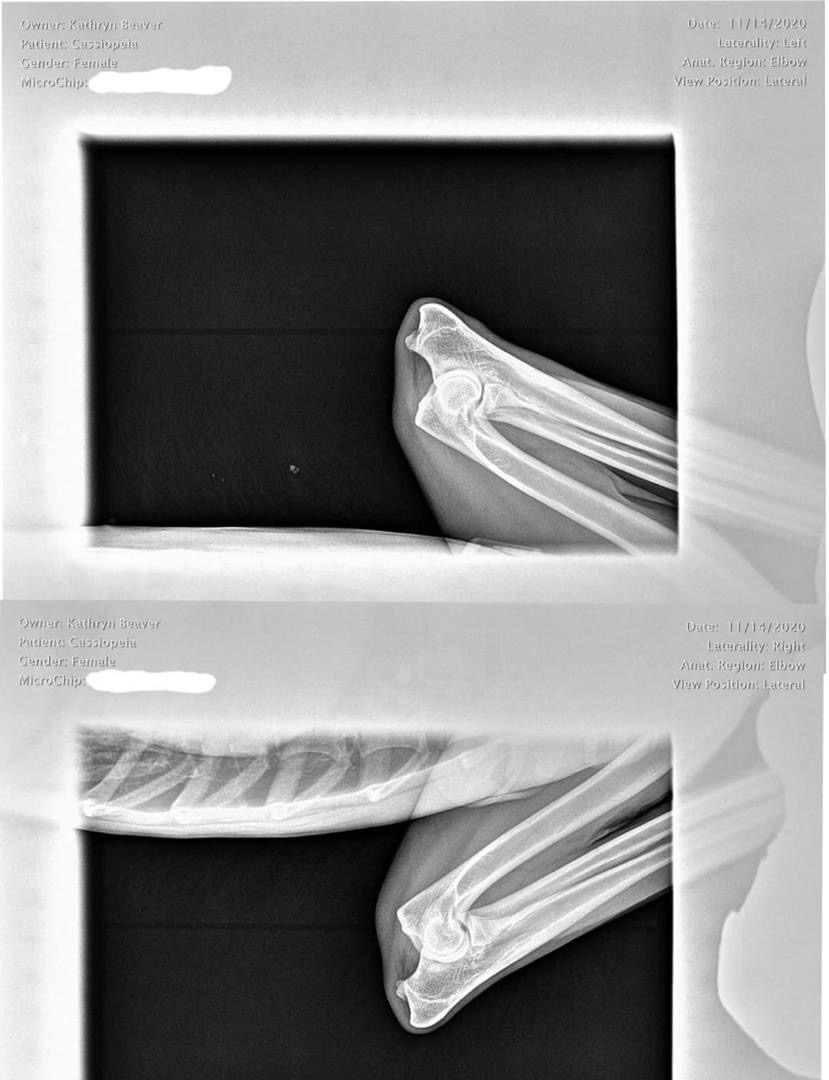

Cassie Elbow X-Ray

Elbow X-Ray Results

OFA Elbow Evaluation: Normal